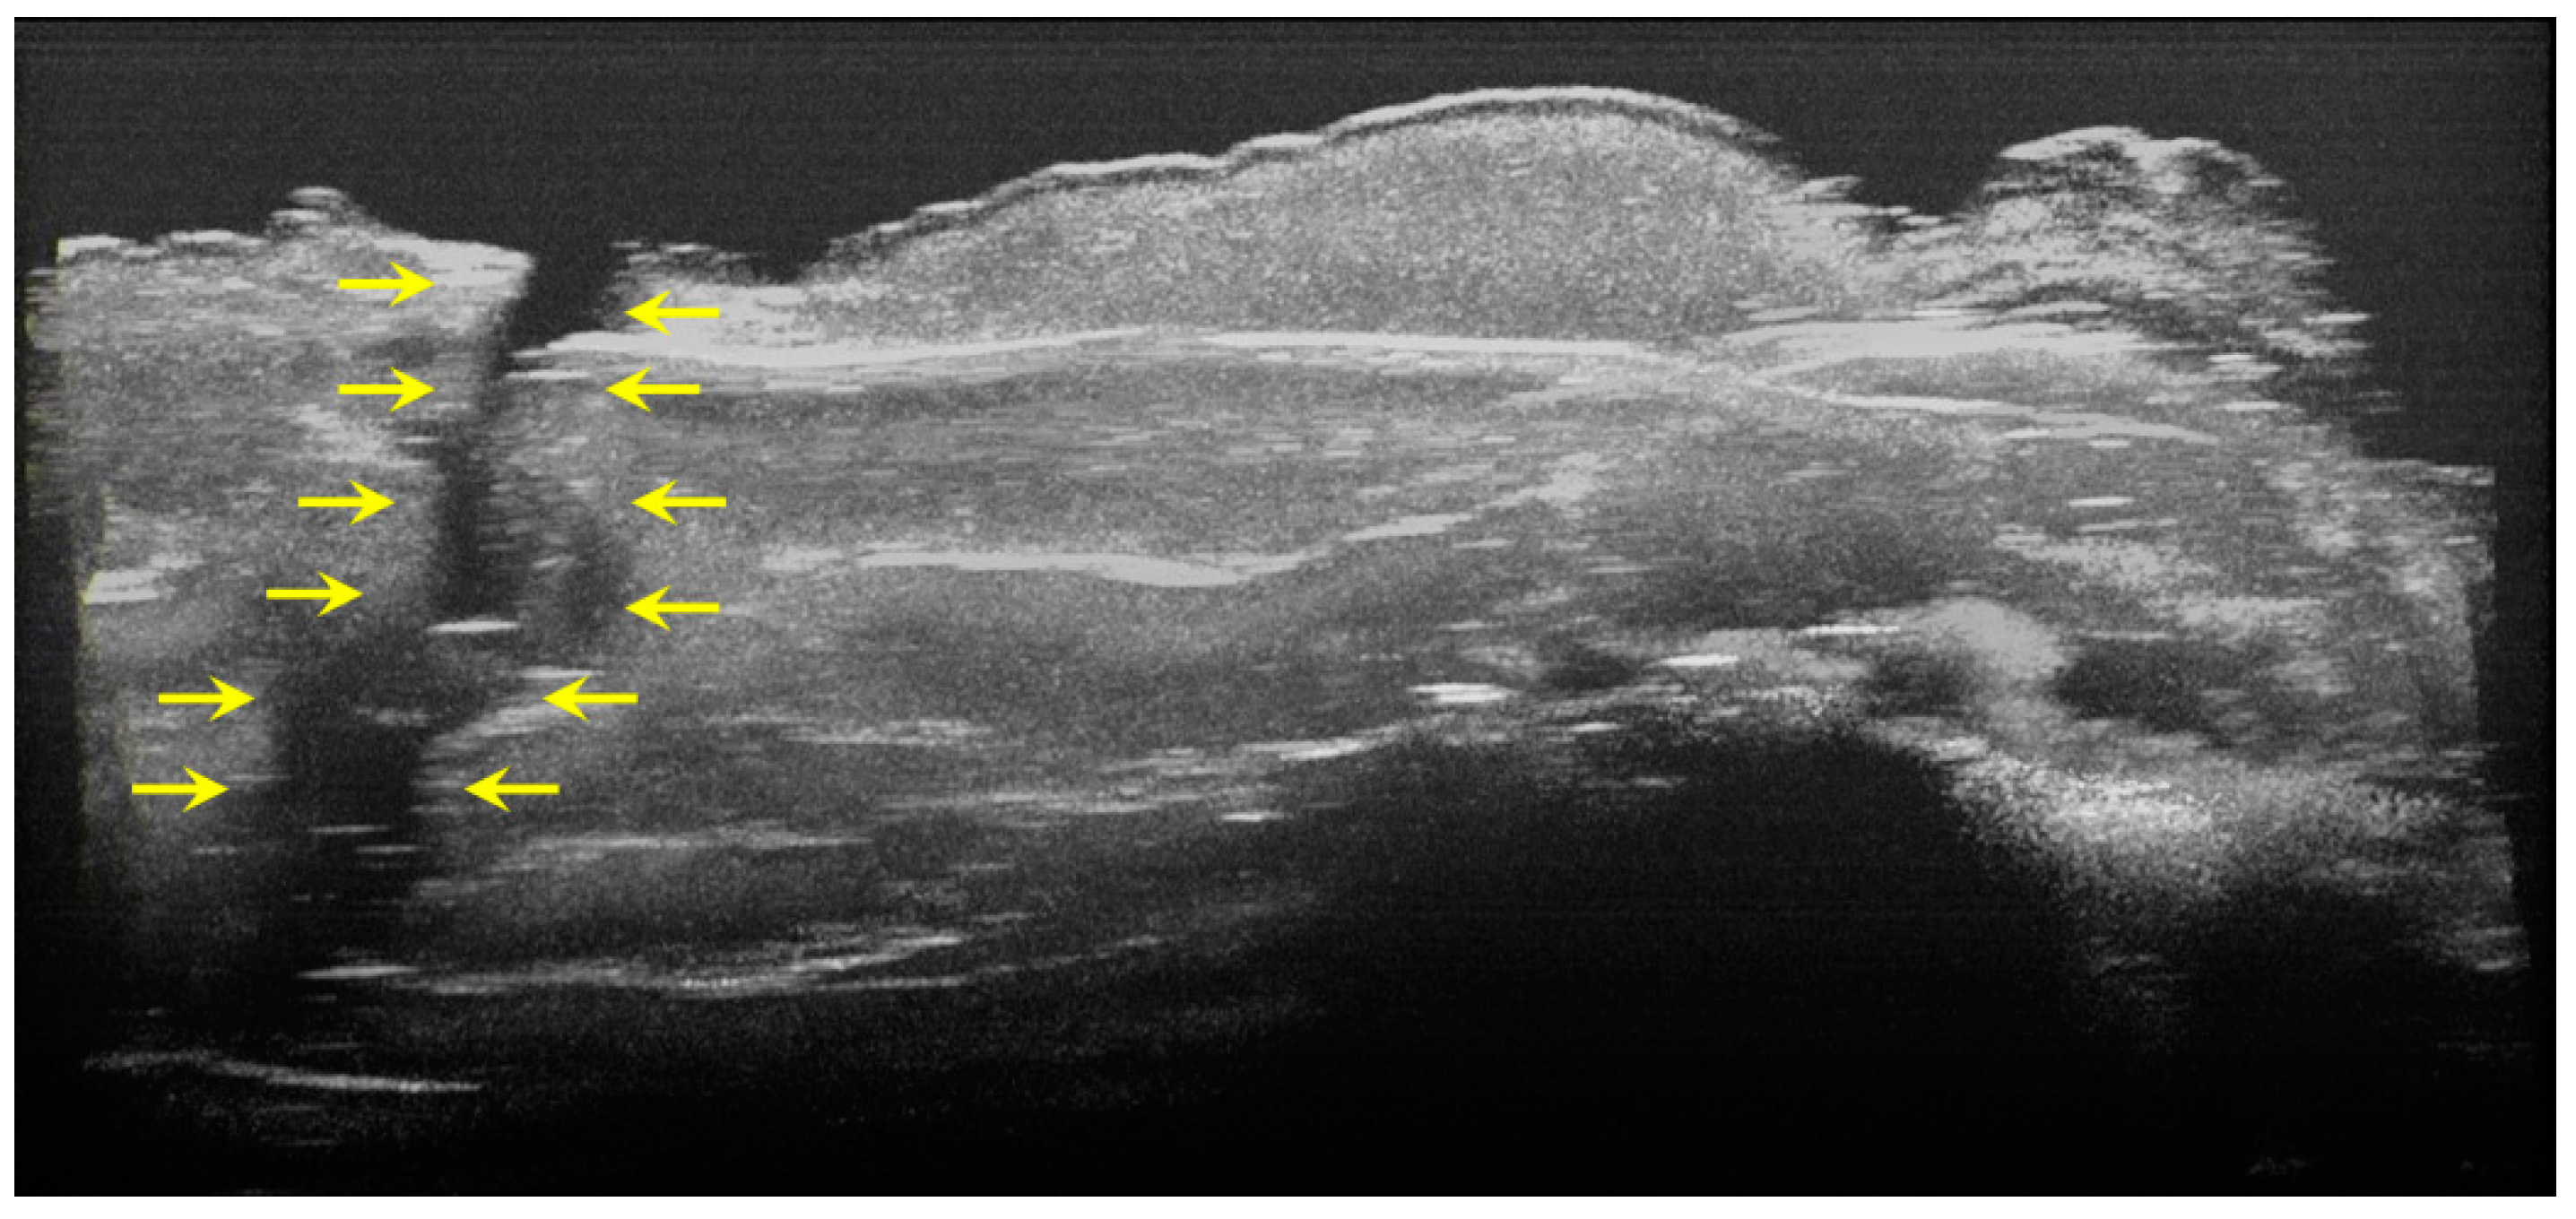

The image processing using ImageJ software showed the spatial disposition and extent of the hypomineralization lesions and hypoplasia (Figure 6, Figure 7, Figure 8 and Figure 9).

Figure 9.

Volumetric reconstruction (in ImageJ) of a hypoplasia lesion. The yellow arrows indicate the affected area, defined by a discontinuity of the enamel at the surface of the tooth; this lesion extends beyond the dentinoenamel junction.